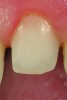

Fig 2. Photograph of a no-preparation to practically preparationless Class I veneer preparation.

Figure 2

CL-I is the purest form of no-preparation or practically prep-less veneers, but can include a discreet finish line or only a loupes-detectable margin (Figure 1). The term addition veneers frequently describes this preparation design today. In this classification, 95% to 100% of enamel volume remains after preparation, and no dentin is exposed. Ideal whenever possible, preparation must be completely and only in enamel.

This preparation type can be easily achieved using a bis-acrylic preparation guide created from a putty or silicone matrix of the diagnostic wax-up, which can be applied to the teeth.49,50 Depth cuts of 0.5 mm for CL-I are placed into the incisal and facial aspects of the bis-acrylic preparation guide, which should result in the depth-cutting bur not touching the tooth, and the clinician should consider removing the aprismatic enamel and placing a practically undetectable finish line (Figure 2 and Figure 3) to aid ceramists in determining margin placement. These depth-cutting grooves minimize potential for over-preparation.